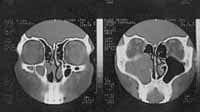

Antecedente quirúrgicos: resección endoscópica de lesión polipoide en antro maxilar izquierdo en abril del 2000 sin informe anatomopatológico conocido. Por recidiva del cuadro obstructivo nasales realiza tomografía de senos paranasales que muestra lesión de tejidos blandos ocupando el antro maxilar nuevamente (Figura 1A y 1B). En octubre del mismo año se realizó nueva resección por vía Cadwell-Luk cuyo informe de patología indica inicialmente adenocarcinoma bien diferenciado. La revisión de las placas y bloques de parafina confirma ameloblastoma de patrón folicular. No hay antecedentes de odontectomía de terceros molares incluidos (Figura 2). Resto de antecedentes negativos.

Lesión de tejidos blandosFigura 1A. Tomografía que evidencia lesión de tejidos blandos ocupando antro izquierdo con extensión a paredes posterior y medial.

compromiso de pared medial y posiblemente del piso orbitarioFigura 1B. Tomografía que evidencia compromiso de pared medial y posiblemente del piso orbitario.

Laboratorios prequirúrgicos normales, panorámica sin evidencia de lesiones óseas y nueva TAC que confirma lesión de tejidos blandos ocupando el antro maxilar izquierdo y comprometiendo sus paredes medial y posterior. Defecto óseo pared anterior por antecedente quirúrgico.